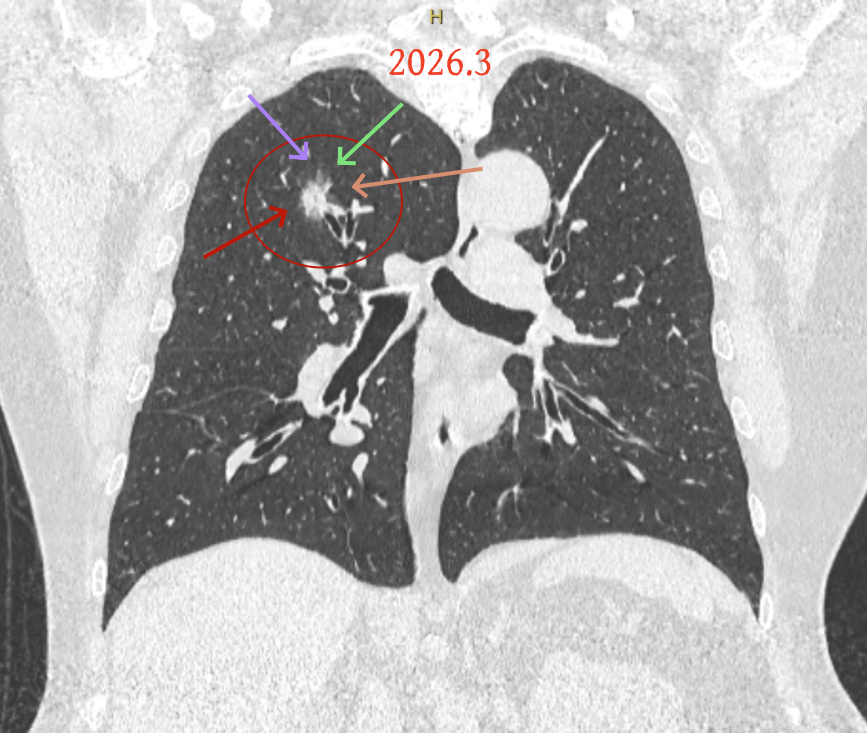

但病灶B却显然进展!变成以实性成分为主的了!

两处均有进展,混合密度这处更显著些。那要考虑手术了的。之前也有碰到较短时间内进展是伴炎症或纤维增生的,但我们不能赌。建议手术为宜。意见供参考!

再看2026年3月最近复查时不同层面病灶A的细节影像特征:

微小血管走向病灶,磨玻璃的密度淡而较纯。

病灶A以及他处磨玻璃结节其实进展都是不明显的,略与2022年比,病灶A稍显明显点。病灶B开始时极淡,之前进展虽有但也甚微,直到2025年9月仍是磨玻璃成分为主,只是点状少许密度稍高成分。但在最近半年内却显然进展!若从影像上判断,基本上就得是浸润性腺癌了。那有几点:一是必不能再随访;二是大小来看仍是1A期;三是从快速进展来说,可能含有部分高危亚型,比如微乳头或实体型等;四是他处的磨玻璃结节以及病灶A显然不能用病灶B的转移来解释,仍考虑是多原发早期肺癌。

这是较为少见的一个病例,磨玻璃为主,而且一直瘤肺边界欠清晰的病灶何以会在之前三年均极缓慢微小变化的情况下,近半年却快速进展呢?从影像细节上看,我们能否进一步分析哪种纯磨玻璃结节可能会较快进展?结合本例,我个人的考虑是:1、病灶整体显得是磨玻璃密度,但灶内并不均匀,就如磨玻璃密度中混入细沙状;2、整体轮廓虽然较清但瘤肺边界相对来说却并不太清晰;3、邻近有血管紧挨,而且与病灶这间缺乏间隙;4、病灶密度不高,没有明显实性成分,却有灶内有细支气管通气征,说明肿瘤成分具有收缩力,却与纯磨的收缩不匹配(纯磨一般不太会有明显收缩力)。如果有上面这些特征可能要提高警惕,一是适当较短的随访间隔,二是影像细节变化要更加注意,开始变化意味着已经进入发展期,而非蛰伏期。当然是否在2025年9月时定得手术了?如果是孤立性的病灶B,且位置位于能简单楔形切除的位置,那是可以考虑的。但位置深、两肺多发,切除范围不小,再今年据肺癌诊疗指南中说的混合磨玻璃结节实性成分不足25%是非侵袭性病变,且几乎不会转移,那么按原则仍再随访显然是可以的。本例的随访变化再次表明磨玻璃密度肺癌的诊疗个体化之路仍是很漫长的,按指南原则的随访或诊疗显然不足以覆盖所有病例,总结与经验积累永远在路上。